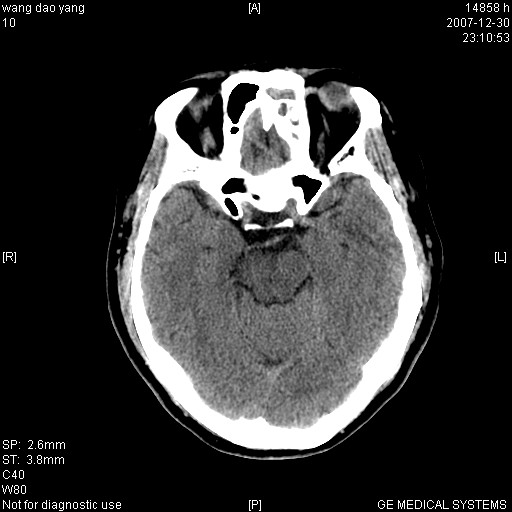

因外伤做ct

1。左侧筛窦蝶窦少量积液,2。右眼眶视神经鞘瘤可能性大,建议增强一下

肌圆锥内占位性病变,血管瘤可能性大。

1 病灶位于肌圆锥内,从第一帧看,和视神经关系不紧密。

2 病灶边界光整,形态欠规则。

3 病灶密度明显高于同层面的正常软组织。

外伤的话首先考虑球后血肿!!

肌圆锥内类软组织密度影,边缘清楚,位于视神经上方,考虑:炎性假瘤可能性大.

建议:强化扫描.

病灶形态不规则,临床有外伤史,支持考虑:球后血肿!!!

考虑右侧视神经脑膜瘤或血管瘤,建议增强进一步检查。

考虑右侧视神经脑膜瘤或视神经胶质瘤,建议增强进一步检查鉴别。

考虑右侧视神经鞘瘤,脑膜瘤或纤维瘤。

球后肌锥内小团块状软组织密度影(性质待定);建议:行ct增强扫描或mri检查。